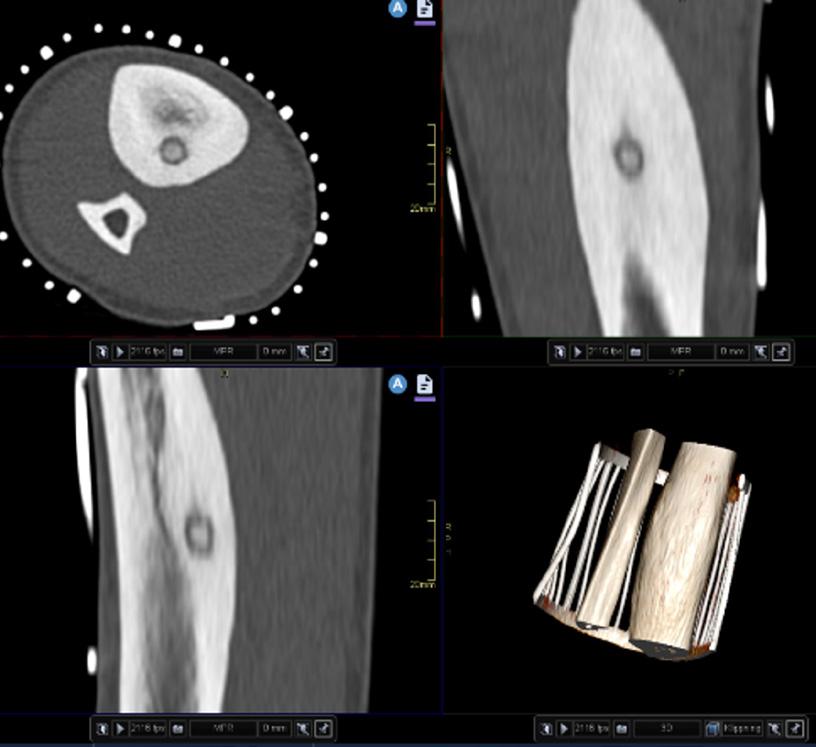

Muskuloskeletala interventioner görs både med diagnostiskt och terapeutiskt syfte där oftast datortomografi, genomlysning och ultraljud används för vägledning. Magnetresonanstomografi (MRT) som har en utmärkt kontrastupplösning har blivit en efterfrågad teknik för muskuloskeletala interventioner. I diagnostiskt syfte utförs radiologivägledda punktioner och biopsier medan det i terapeutiskt syfte utförs radiologivägledda ablationer av olika tumörförändringar. Nervblockader och andra injektioner kan göras både i diagnostiskt och terapeutiskt syfte.

RADIOLOGILEDDA BIOPSIER

En väl utförd biopsi är avgörande för diagnostik av muskuloskeletala förändringar, särskilt vid diagnostik och hantering av bentumörer. Även om moderna radiologiska avbildningstekniker är viktiga för differentialdiagnos är en histopatologisk undersökning vanligtvis nödvändig för att planera vidare behandling.1,2 Öppen biopsi har traditionellt varit guldstandard för muskuloskeletala lesioner. Den ger tillräckligt material för histologiska och immunohistokemiska undersökningar i de flesta fall vilket resulterar i en slutlig diagnos.3 Att utföra en öppen biopsi kan däremot vara ett svårt ingrepp med en betydande risk för komplikationer speciellt i vertebra-

la och djupt belägna förändringar.4,5 Rollen för öppen biopsi har minskat under de senaste åren till förmån för mindre invasiva tekniker med adekvat tillgång till vävnad utan samma omfattning av komplikationer.6 Som alternativ till öppen biopsi har radiologivägledda perkutana biopsier vunnit popularitet på grund av deras mindre invasiva tillvägagångssätt, färre komplikationer och goda utbyte. Perkutan nålbiopsi utförs generellt polikliniskt eftersom generell anestesi sällan är nödvändig. Kostnad och tidsåtgång brukar vara betydligt mindre än vid en öppen biopsi och det är mindre risk för tumörspridning, infektioner och sårkomplikationer.7 Dessutom ger radiologivägledning en bättre tredimensionell orientering och hantering av biopsiområdet.8 På grund av alla dessa faktorer har radiologiledda biopsier i de flesta fall blivit standard för att få en histopatologisk diagnos.9,10

RADIOLOGIVÄGLEDDA ABLATIONER

Interventionell radiologi har revolutionerat den lokala hanteringen av bentumörer och erbjuder nya minimalinvasiva alternativ till kirurgi och strålbehandling. Dess roll har kontinuerligt ökat under de senaste åren för behandling av godartade tumörer och även vissa maligna sådana, särskilt i palliativa situationer. Utvecklingen av skyddstekniker och nya ablationsteknologier som kryoablation har bidragit till att utöka rollen för den interventionella radiologin till nya användningsområden inom muskuloskeletal onkologi.11 Den klassiska behandlingen av muskuloskeletala tumörer brukar innefatta kirurgi för att avlägsna lesionen och förstärka

benet om nödvändigt och strålbehandling för att fullborda resultatet av operationen.12–16 Denna metodik kan dock vara svår eller omöjlig för vissa patientgrupper med dåligt allmäntillstånd. Där kan i stället perkutana radiologivägledda ablationer utgöra ett värdefullt alternativ för vissa muskuloskeletala lesioner.15

Sedan början av 1990-talet har perkutan ablationsteknik använts för hantering av benigna bentumörer, initialt för osteoidosteom.16 Perkutan behandling vid denna indikation är vanligtvis botande efter en enda behandling och har en mycket låg komplikationsfrekvens.17 Den goda erfarenheten av radiofrekvensablation har resulterat i att andra perkutana radiologistyrda tekniker har försökts mot andra benigna bentumörtyper. Fortsatt teknisk utveckling gör att perkutana bildstyrda tekniker nu används allt oftare vid kontroll och behandling av olika godartade tumörer och metastaser med många fler indikationer.18

Bild 1. En okänd sklerotisk förändring dorsala kaudala omfånget av kotkroppen som punkteras av en benbiopsi nål under DT-vägledning. Bild 2. En intrakortikal hypodens förändring med sklerotiskt nidus och utseende som osteoid-osteom. En radiofrekvensablation utfördes i centrala nidus av förändringen. Uppföljande undersökningar visade god effekt utan recidiv. Bild 3. Patient med kronisk tendinos i Achilklessenan med kärlinväxt i den spolformiga senan. Injektion av aethoxysklerol för att sklerosera patologiska kärlkluster. Bild 4. Nervrotsblockad i L4. Kontrastinjektion visar att nålen ligger på rätt plats i nervskidan där den utgår från spinalkanalen. Mepivacaine och Depo-Medrol injicerades för smärtlindring och långvarig inflammationsdämpning.